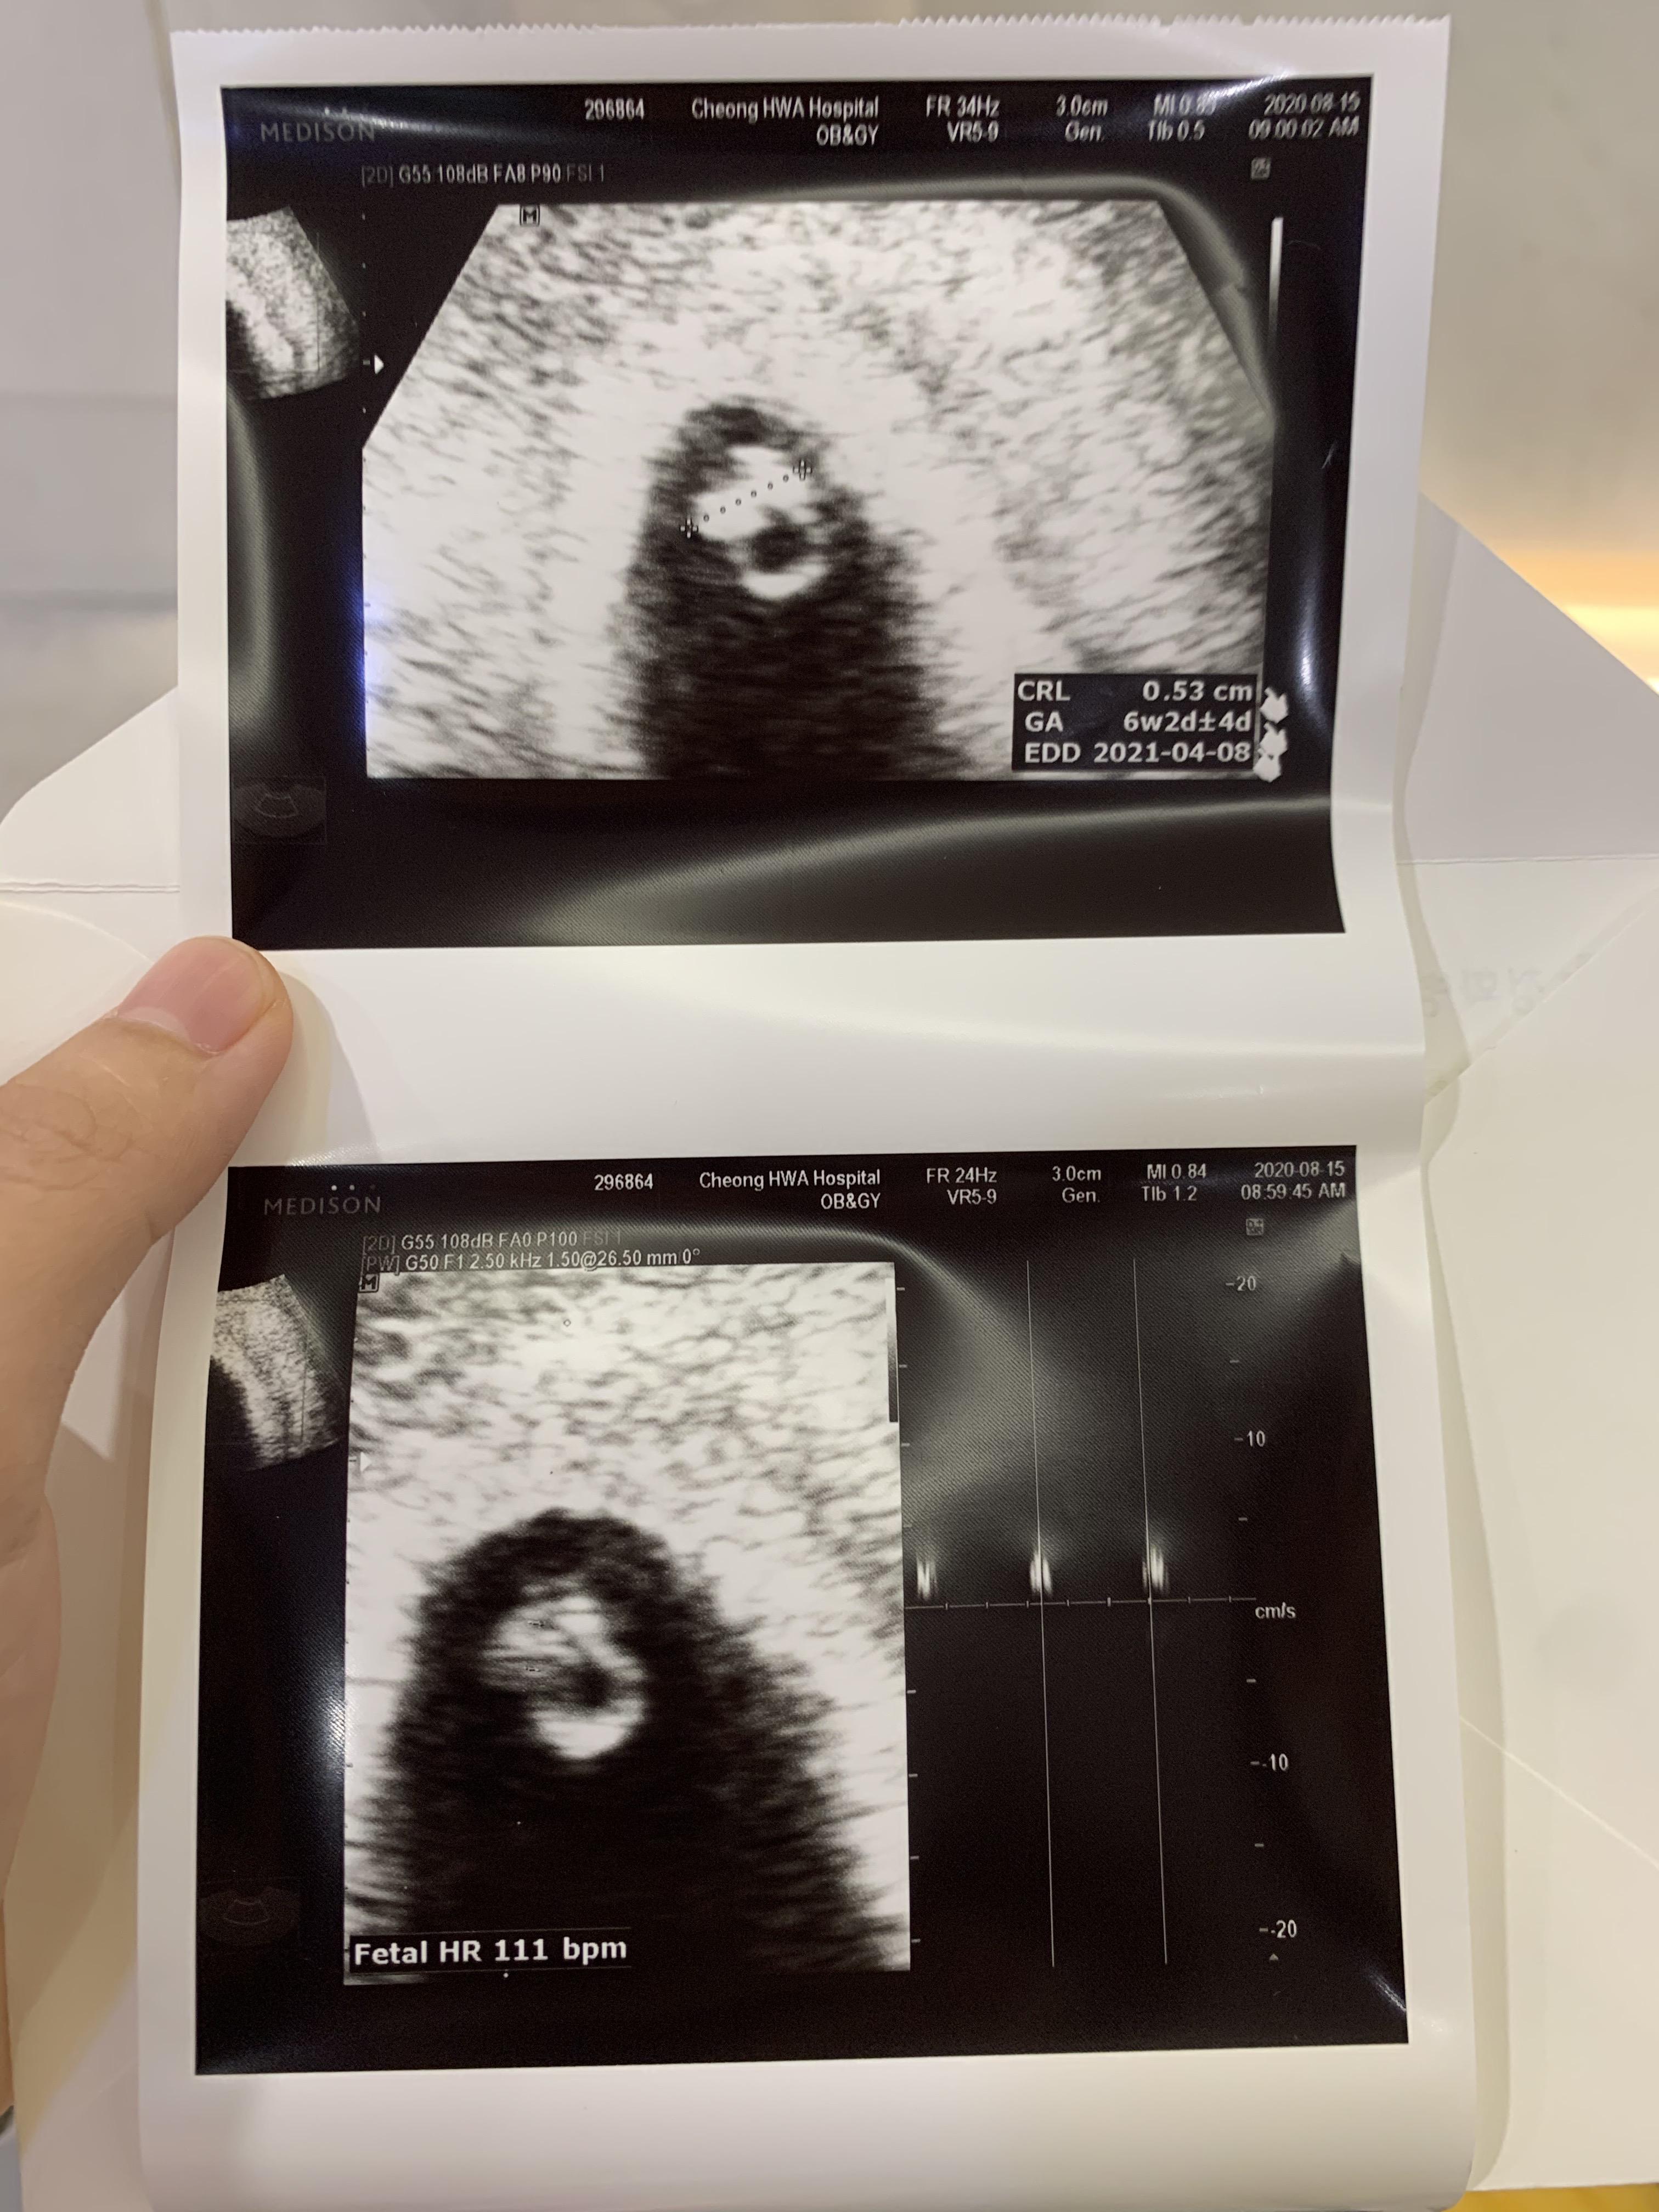

두둥!

난황에 배아까지 봅니다!

게다가 반짝반짝 심장소리까지 들었어요!

아기집은 두 배로 커져서 2센티 정도 되고,

아기 크기가 0.5cm정도 되더라고요.

심장소리 츄큐츄큐 111bpm

추정 주수는 6주로 알고 갔는데, 3일 빨라진

6주 3일로 확인하고 돌아옵니다.